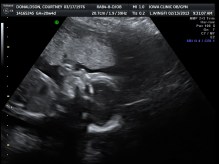

ULTRASOUND_7 February 13, 2013 by Courtney Leave a comment ← Previous Image Next Image → Like Loading...